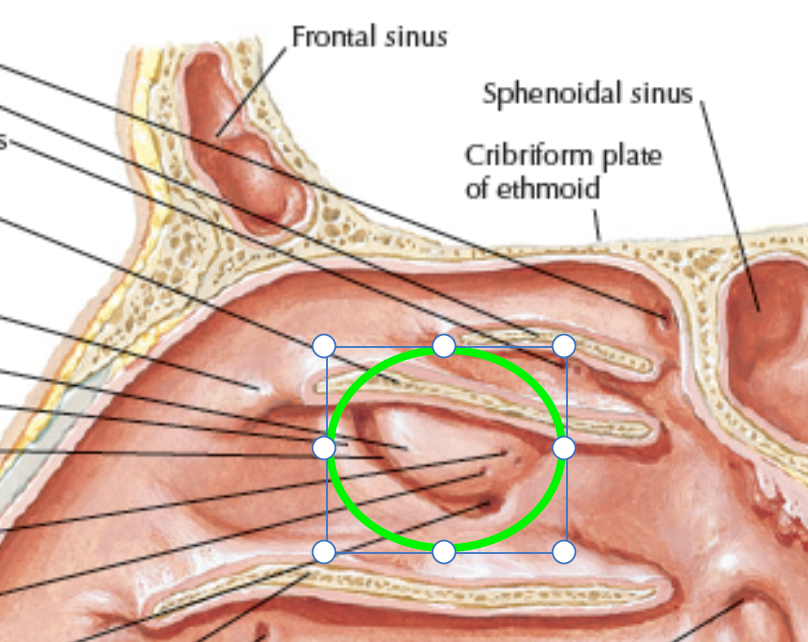

Ethmoid bone

- Cribriform plate

- Olfactory n. (CN I)

- superior and middle Nasal concha

Hypophyseal fossa

腦下垂體在這

Nasal septum (鼻中膈)

- nasal sepal cartilage

- perpendicular plate of ethmoid

- vomer

Paranasal sinuses

鼻旁竇,濕潤呼吸的空氣

Frontal sinus

神經皆CN V1

- Anterior ethmoid a.

- Supraorbital a./n.

- Supratrochlear (滑車上) a./n.

Sphenoid sinus